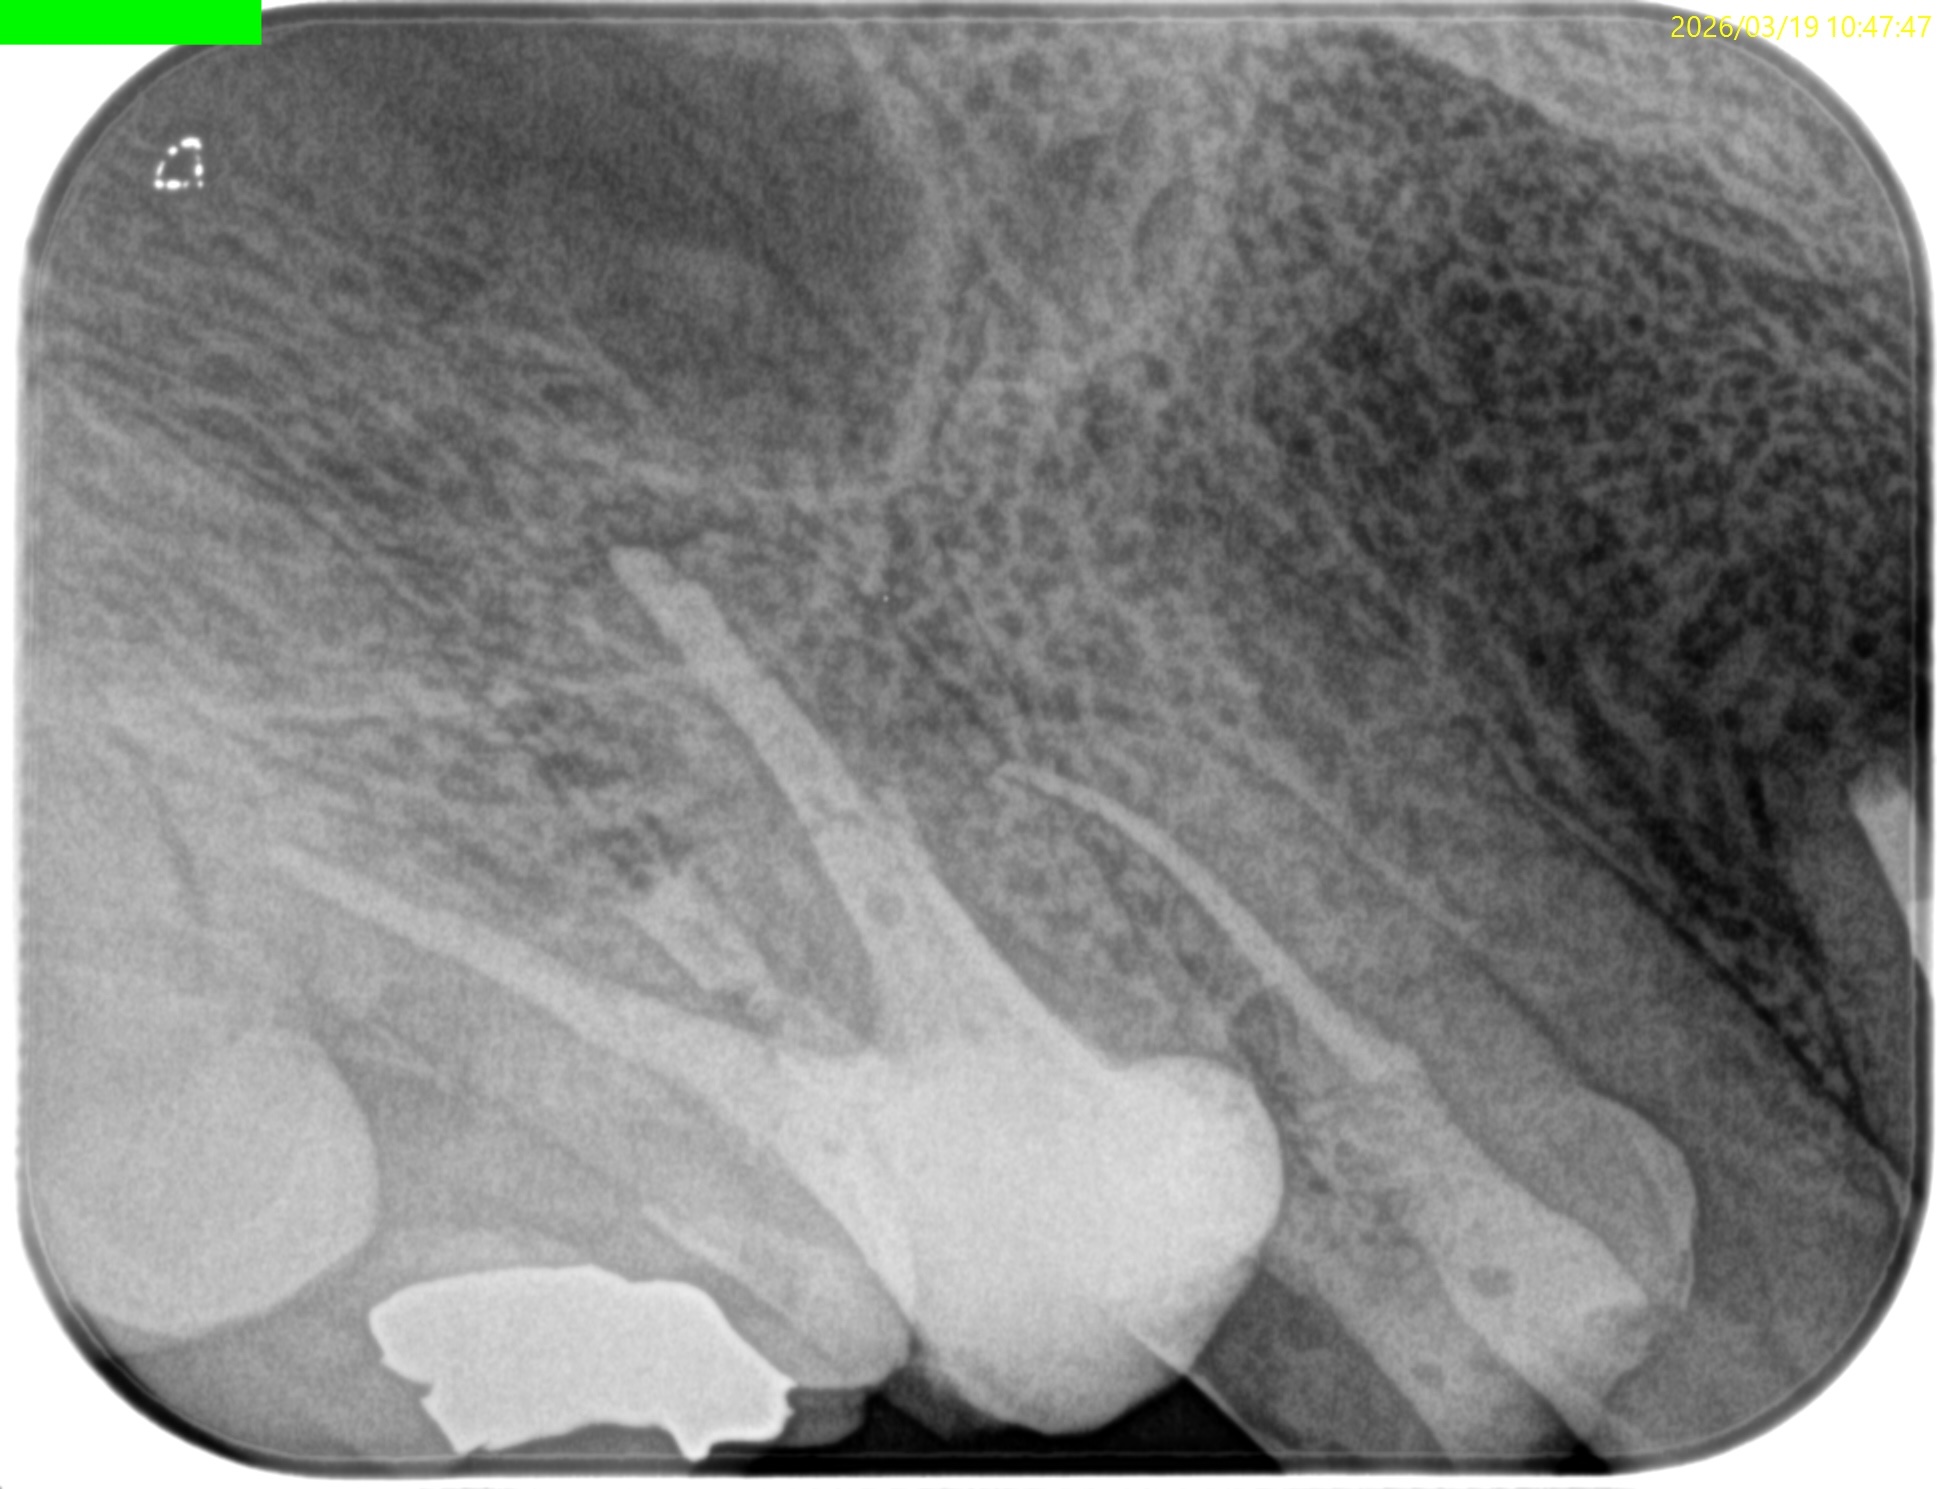

充填後、CBCTとPAを撮影した。

問題はないだろう。

#3 MB Apicoectomy 1yr recall(2026.3.19)

歯槽骨の欠損、Sinus tract, 臨床症状は消失した。

最終補綴もOKで、経過観察も終診とさせていただいた。